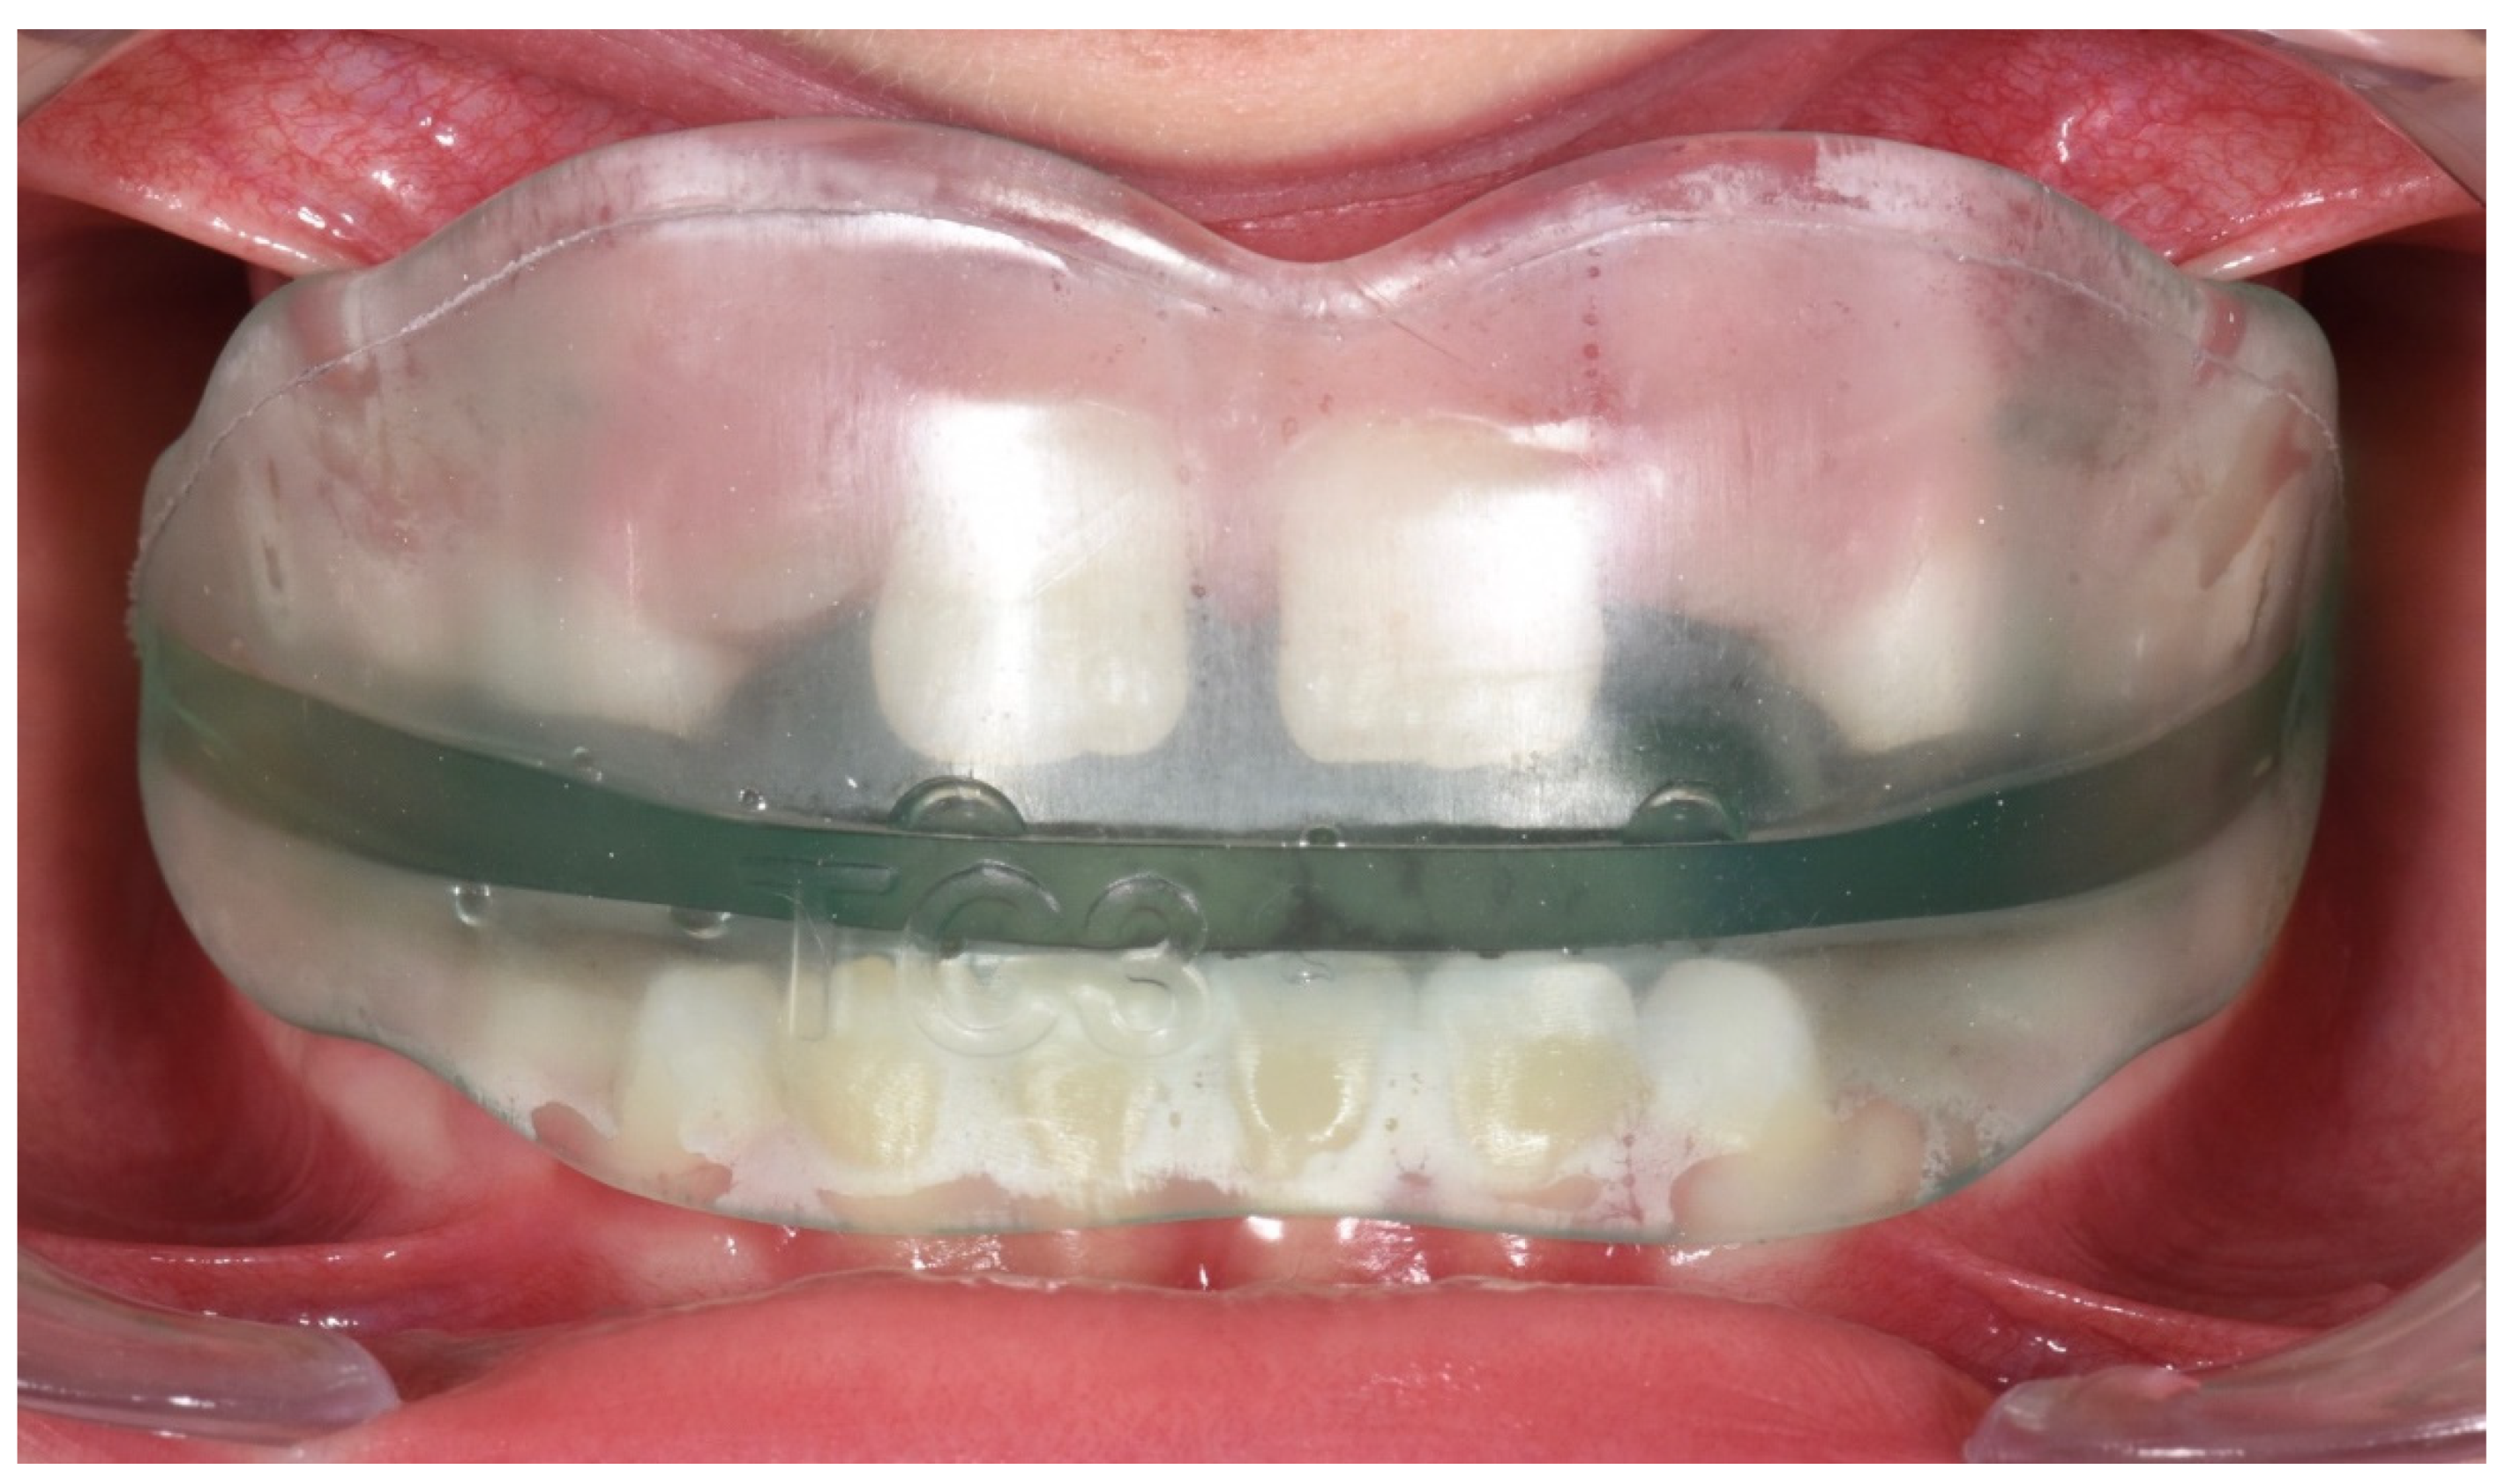

2.1. AMCOP Bio-Activator Devices

2.1.1. Bio-Activator for young children

2.1.2. First Class Bio-Activator

2.1.3. Second Class (SC) Bio-Activator

2.1.4. Third Class (TC) Bio-Activator

2.1.5. Novel Bio-Activators